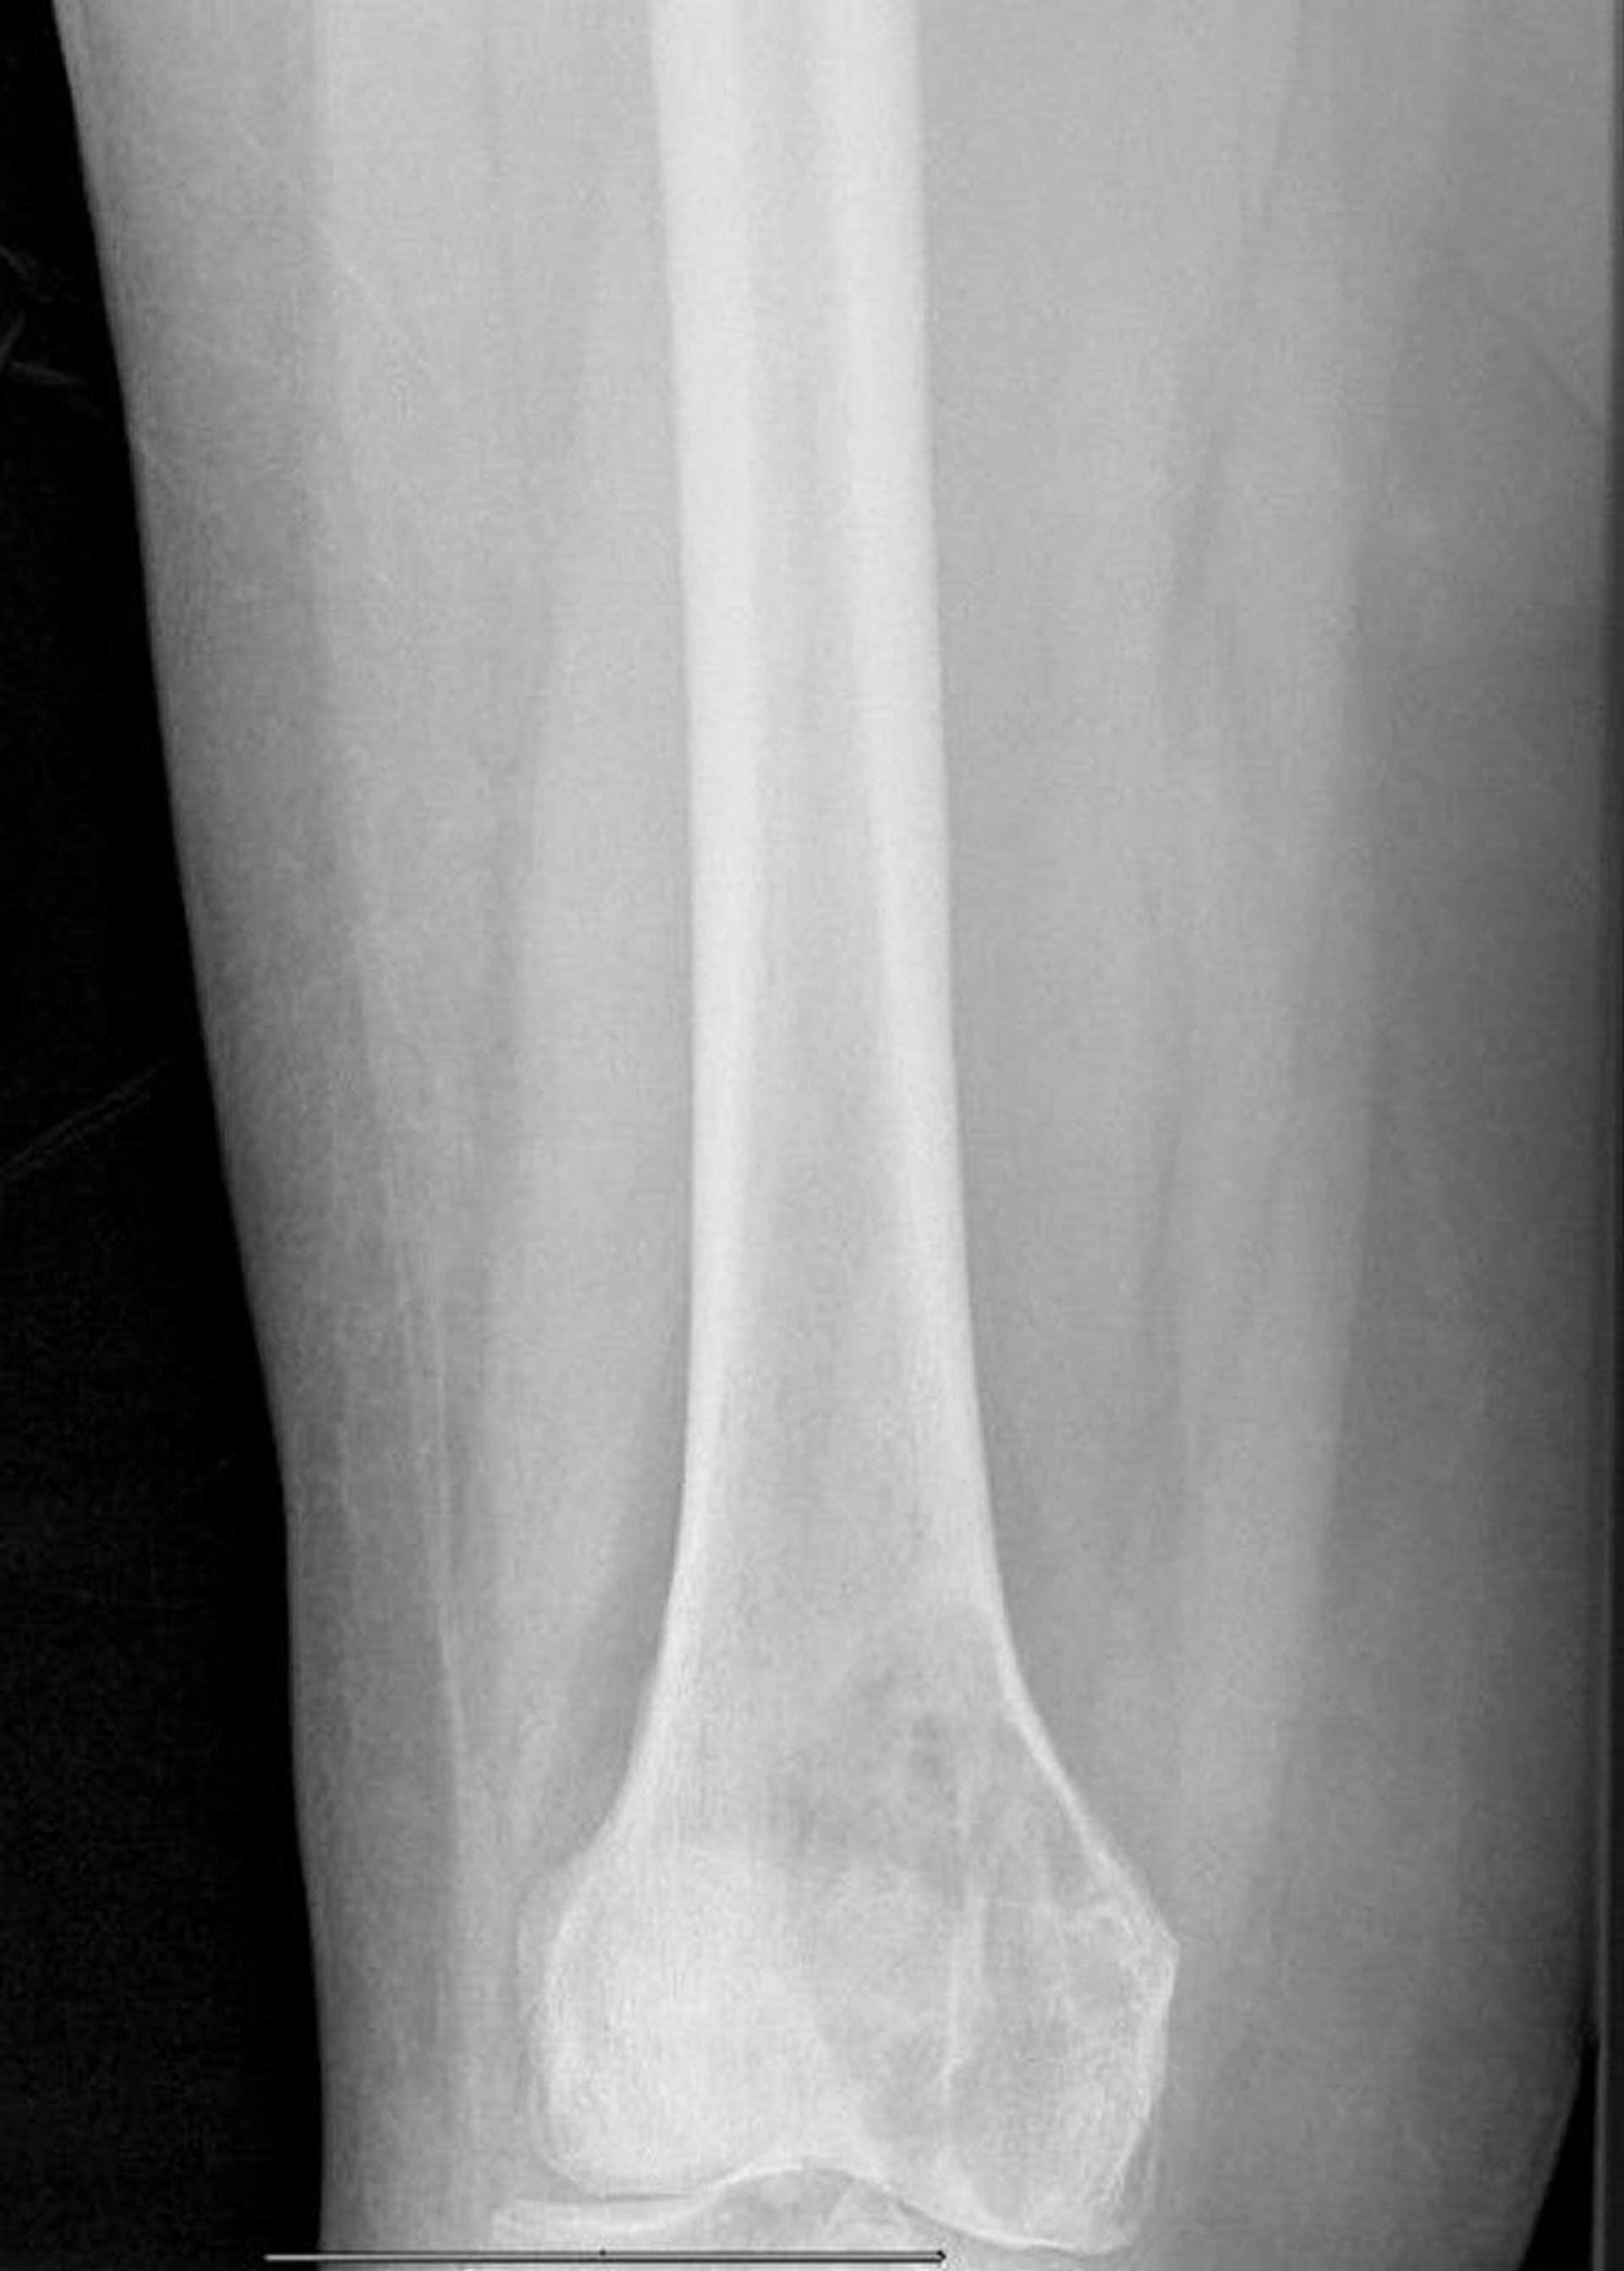

Lytic Metastasis in the Distal Femur

This radiograph shows a large metastatic lytic lesion of the femoral medial condyle with impending pathologic fracture.

Image courtesy of Michael J. Joyce, MD, and David M. Joyce, MD.